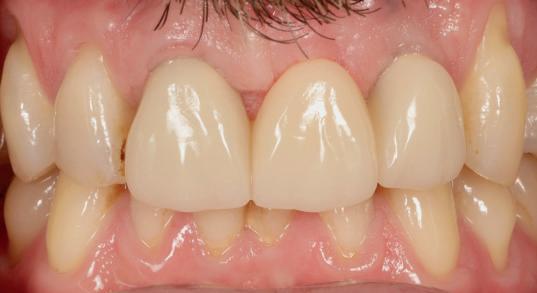

Adults could one day grow their own replacement teeth instead of having fillings – as scientists make a key discovery. This research offers a potential way to repair teeth and a natural dental treatment alternative.

Unlike implants and fillings, which are fixed and cannot adapt over time, a labgrown tooth made from a patient’s own cells could integrate seamlessly into the jaw and repair itself like a natural tooth.

In the latest study, the King’s team, in collaboration with Imperial College London, made a key discovery on the environment needed to grow teeth in the lab. They have now successfully introduced a special type of material that enables cells to communicate between each other. This means that one cell can effectively ‘tell’ another to start differentiating into a tooth cell. This mimics the environment of growing teeth and allows scientists to recreate the process of tooth development in the lab.

Having successfully created the environment needed to grow teeth, scientists are now faced with the challenge of getting them from the lab to a patients’ mouths.

Xuechen added: “We have different ideas to put the teeth inside the mouth. We could transplant the young tooth cells at the location of the missing tooth and let them grow inside mouth. Alternatively, we could create the whole tooth in the lab before placing it in the patient’s mouth. For both options, we need to start the very early tooth development process in the lab.”